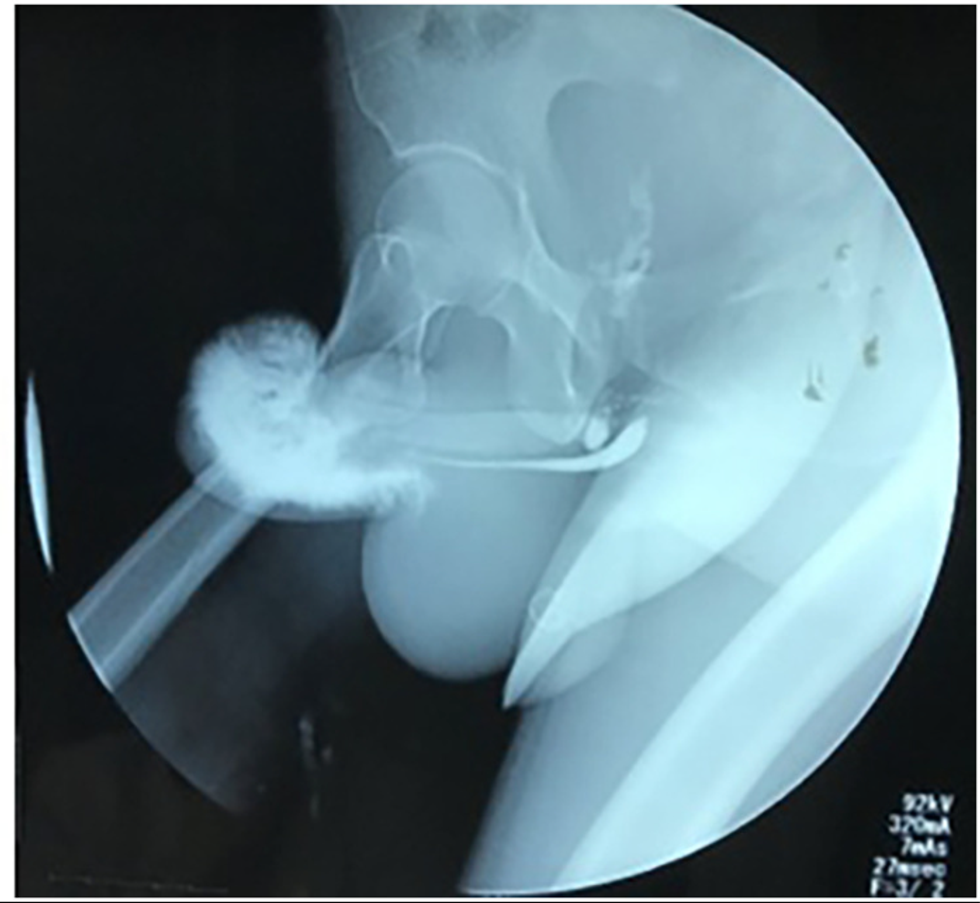

Upon examination, it was revealed that his member had turned purple due to the swelling and that the penis had skewered towards the right, as if to create a question mark-like shape.

If that wasn't enough, doctors also discovered a hematoma, otherwise known as a blood clot, that ran all the way from the tip of his penis to his scrotum. He also had a ruptured urethra which is likely to have impeded the urine flow.

To save the poor fellow's penis the doctors had to operate by first cutting open the penis and fixing the damaged urethra and penis tissue. The blood clot was then drained and he was fitted with an 'artificial erection' for an erectile exam.

Luckily for him, he passed the test and did have any further problems like fluid leakage or a continued bend in his penis. He was discharged after five days in hospital but had to urinate through a catheter for 21 more days.